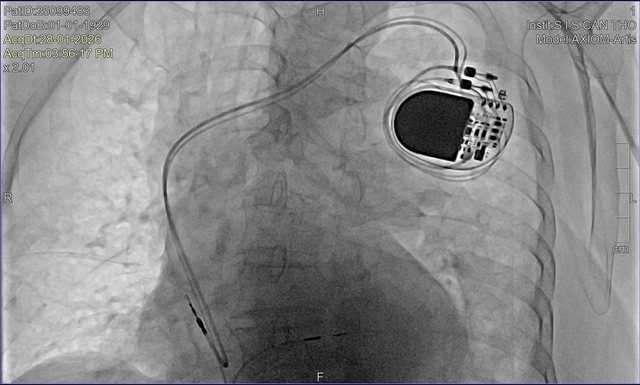

Trước tình thế đó, ê-kíp bác sĩ Bệnh viện Đa khoa Quốc tế S.I.S Cần Thơ đã nhanh chóng đặt máy tạo nhịp tạm thời để ổn định huyết động, đồng thời thực hiện các thăm dò chuyên sâu, trong đó có chụp mạch vành bằng DSA. Sau khi đánh giá toàn diện và hội chẩn, các bác sĩ thống nhất chỉ định cấy máy tạo nhịp vĩnh viễn bằng kỹ thuật bó nhánh trái – một phương pháp tiên tiến hiện chưa phổ biến rộng rãi.

Cụ bà U100 được cấy máy tạo nhịp vĩnh viễn thành công bằng kỹ thuật tiên tiến.

BS.CKII Nguyễn Mạnh Cường – Phó khoa Nội Tổng hợp Bệnh viện S.I.S Cần Thơ cho biết, đây là bệnh nhân lớn tuổi nhất từng được bệnh viện thực hiện kỹ thuật này. Thách thức không chỉ đến từ tuổi cao mà còn ở đặc điểm rối loạn nhịp phức tạp, đòi hỏi thao tác chính xác và kiểm soát chặt chẽ trong suốt quá trình can thiệp.

Khác với cách tạo nhịp truyền thống, kỹ thuật bó nhánh trái giúp tái lập dẫn truyền điện học gần với sinh lý tự nhiên, bảo tồn chức năng co bóp của thất trái và giảm nguy cơ suy tim lâu dài. Với người cao tuổi, ưu điểm này càng có ý nghĩa khi mục tiêu điều trị không chỉ là kéo dài sự sống mà còn duy trì chất lượng sống.

"Ca can thiệp diễn ra thuận lợi. Sau thủ thuật, nhịp tim cụ ổn định, các triệu chứng giảm rõ rệt. Chỉ sau 4 ngày điều trị, cụ đủ điều kiện xuất viện trong sự xúc động của gia đình", BS. Cường thông tin thêm trong hôm nay (12/2).